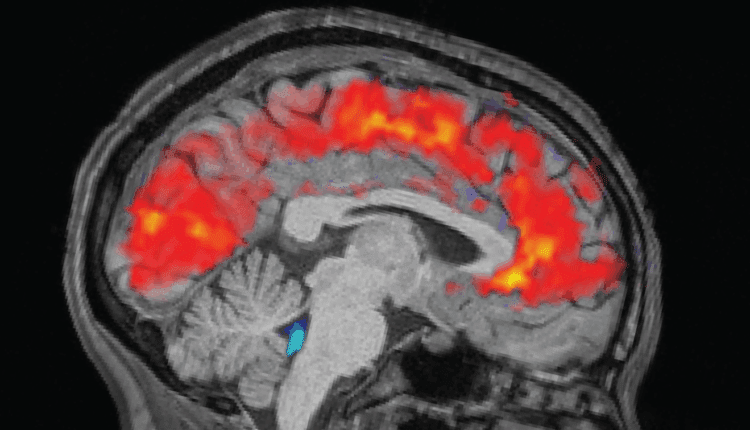

Τα ξεκούραστα άτομα κοιμήθηκαν για 6,5 έως 9 ώρες στο σπίτι, ενώ τα άτομα που στερήθηκαν τον ύπνο έμειναν ξύπνια όλη τη νύχτα στο εργαστήριο. Το πρωί πριν από κάθε δοκιμή, η ομάδα στερέωσε ηλεκτροεγκεφαλογραφικά (ΗΕΓ) καπέλα στους συμμετέχοντες για να καταγράψει τα εγκεφαλικά τους κύματα με ηλεκτρόδια. Ταυτόχρονα, οι συμμετέχοντες υποβλήθηκαν σε σαρώσεις λειτουργικής μαγνητικής τομογραφίας (fMRI) για να αποκαλύψουν μοτίβα στη ροή αίματος και ΕΝΥ στον εγκέφαλο. Οι ανιχνευτές ματιών μέτρησαν το μέγεθος της κόρης των ματιών των συμμετεχόντων.

Όπως αναμενόταν, οι συμμετέχοντες χρειάστηκαν περισσότερο χρόνο για να παρατηρήσουν τα ερεθίσματα όταν ήταν κουρασμένοι και έχασαν τα σημάδια συχνότερα από ό,τι όταν ήταν καλά ξεκούραστοι. Αλλά η ομάδα εξεπλάγη όταν είδε γιγάντιους παλμούς ΕΝΥ στα εξαντλημένα άτομα, παράλληλα με μοτίβα αργών εγκεφαλικών κυμάτων – και τα δύο παρατηρούνται συνήθως στον ύπνο non-REM.

Η ροή του ΕΝΥ συνδέθηκε στενά με το μέγεθος της κόρης του ματιού, με τη μεγάλη εισερχόμενη ροή να ακολουθεί τη διαστολή της κόρης και την εξερχόμενη να έρχεται μετά τη συστολή της κόρης. Αυτή η σύνδεση ήταν πιο έντονη στα άτομα που είχαν στερηθεί τον ύπνο, γεγονός που θα μπορούσε να υποδηλώνει ότι το κυκλοφορικό σύστημα του σώματος στηρίζει αυτή τη σύζευξη, έγραψαν οι συγγραφείς. Οι ροές του ΕΝΥ συνέπεσαν επίσης με τις στιγμές που τα άτομα “έχαναν” την προσοχή τους κατά τη διάρκεια των εργασιών.

“Όταν έχετε αποτυχίες προσοχής… αυτό το υγρό αποβάλλεται από τον εγκέφαλό σας και όταν ανακτάτε την προσοχή, όταν αρχίζετε να ανταποκρίνεστε ξανά στα ερεθίσματα, αυτό το υγρό ρέει πίσω στον εγκέφαλό σας”, δήλωσε ο Zinong Yang, υπολογιστικός νευροεπιστήμονας στο MIT και πρώτος συγγραφέας της μελέτης.

Οι ερευνητές πιστεύουν ότι τα εγκεφαλικά μοτίβα που βλέπουν μπορεί να αντανακλούν τον εγκέφαλο που έχει στερηθεί τον ύπνο και μεταβαίνει σε μια κατάσταση παρόμοια με τον ύπνο, αλλά ενώ είναι ακόμα ξύπνιος. Οι διακοπές στην προσοχή σηματοδοτούν την έναρξη αυτών των εγκεφαλικών διεργασιών που μοιάζουν με ύπνο, αλλά διακόπτονται πριν αρχίσει ο κανονικός ύπνος.